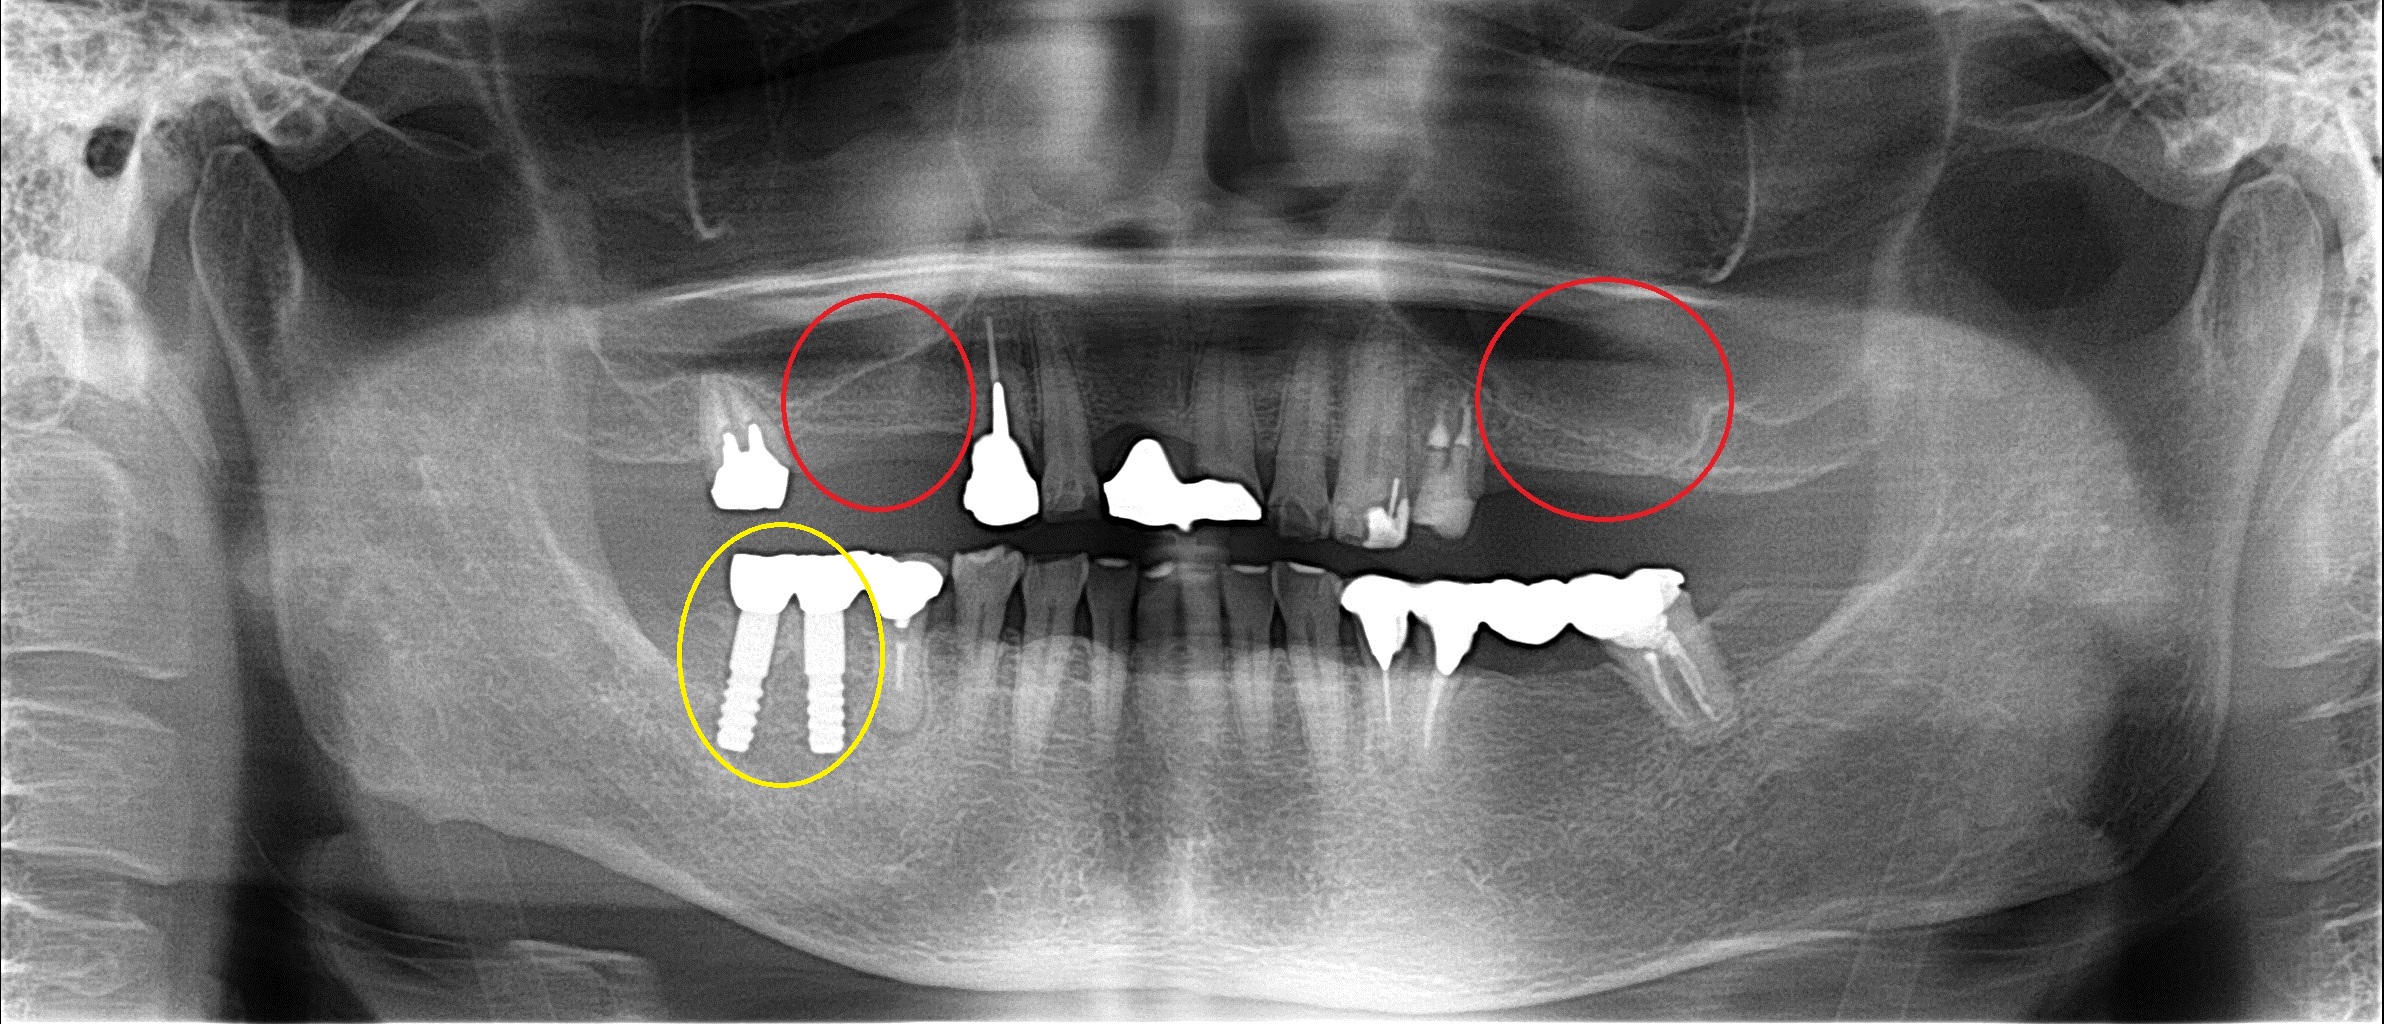

初診来院時 ↓

治療が終わった一昨日 ↓

左右、両方ともに少し骨を造ってインプラント治療しました。